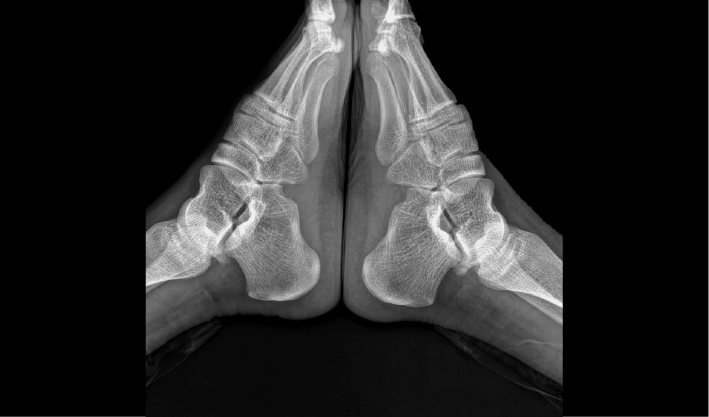

常规DR摄影检查,如:胸片位,腹部位,四肢位等。

成熟优秀的动态成像技术,在透视下实时观察内部器官运动状态,并可快速高清点片,动静结合,多视角精准观察病灶。